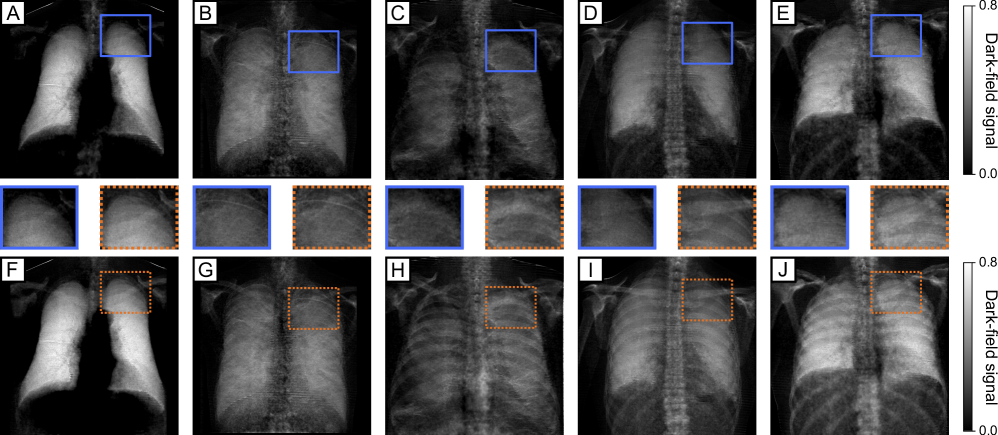

The proposed segmentation-based BHC described was applied to 174 clinical dark-field chest radiographs from patients not included in the segmentation model’s training or validation cohorts. Representative results from five patients – one healthy subject, two with COPD of varying severity, and two with COVID-19 pneumonia – are shown in Fig. 3.

In the uncorrected images, pronounced beam hardening-induced signals from osseous structures, particularly ribs and clavicle, are visible across the lung. These structured artifacts introduce marked inhomogeneity and obscure the overlapping lung parenchyma. Following BHC, these bone-induced features are substantially reduced, yielding a more homogeneous signal distribution and improving visualization of the pulmonary microstructure. Insets highlight the segmented rib and clavicle regions, further illustrating artifact suppression by the BHC.